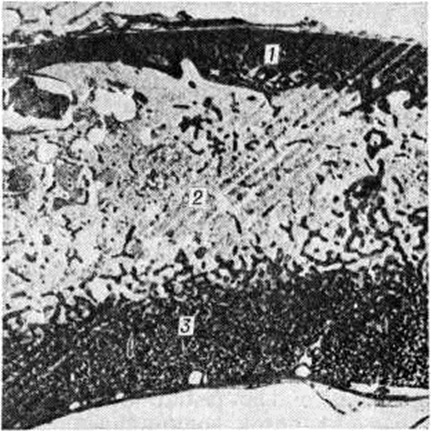

Рис. 2.

Гистотопограмма сагиттального распила теменной кости при болезни Педжета: спонгизация компактных пластинок (1, 3), средний отдел кости (2) содержит жировую и кроветворную ткани, внутренняя пластинка заметно утолщена, состоит из однородной мелкоячеистой губчатой костной ткани (3); окраска гематоксилин-эозином, × 1,5.

Кости лицевого черепа поражаются сравнительно редко. Заболевание характеризуется возникновением на ограниченном участке кости очага из волокнистой остеогенной ткани и простейших, слабо обызвествленных губчатых структур. Постепенное увеличение зоны поражения приводит к утолщению, спонгиозированию костей, изменению величины и формы черепа (рисунок 1). Выраженность патологический изменений у разных больных неодинакова. Поверхность поражённого отдела кости красноватая, под периостом видны множественные мелкие отверстия сосудистых каналов. Рисунок кровеносных сосудов на внутренней поверхности костей черепа сохранен. Изменённая кость достигает 3—6 сантиметров толщины. На распиле видны поля остеосклероза (смотри полный свод знаний), участки разрежения костных структур, островки кроветворной и жировой ткани. В костях черепа преобладают однородные мелкоячеистые структуры, в большем количестве располагающиеся на внутренней костной пластинке (рисунок 2). Анатомо-топографические соотношения между костями черепа постепенно нарушаются. Передняя черепная ямка, скат основания черепа уплощаются (платибазия), боковые отделы средней ямки и задняя черепная ямка прогибаются, затылочная кость оседает на заднюю дугу атланта.